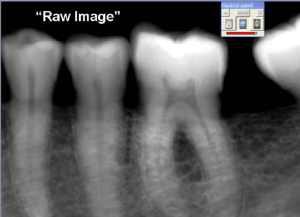

| Software can enhance digital x-rays to highlight different aspects. This is the raw image produced by a Kodak Dental Imaging intraoral X-ray sensor |